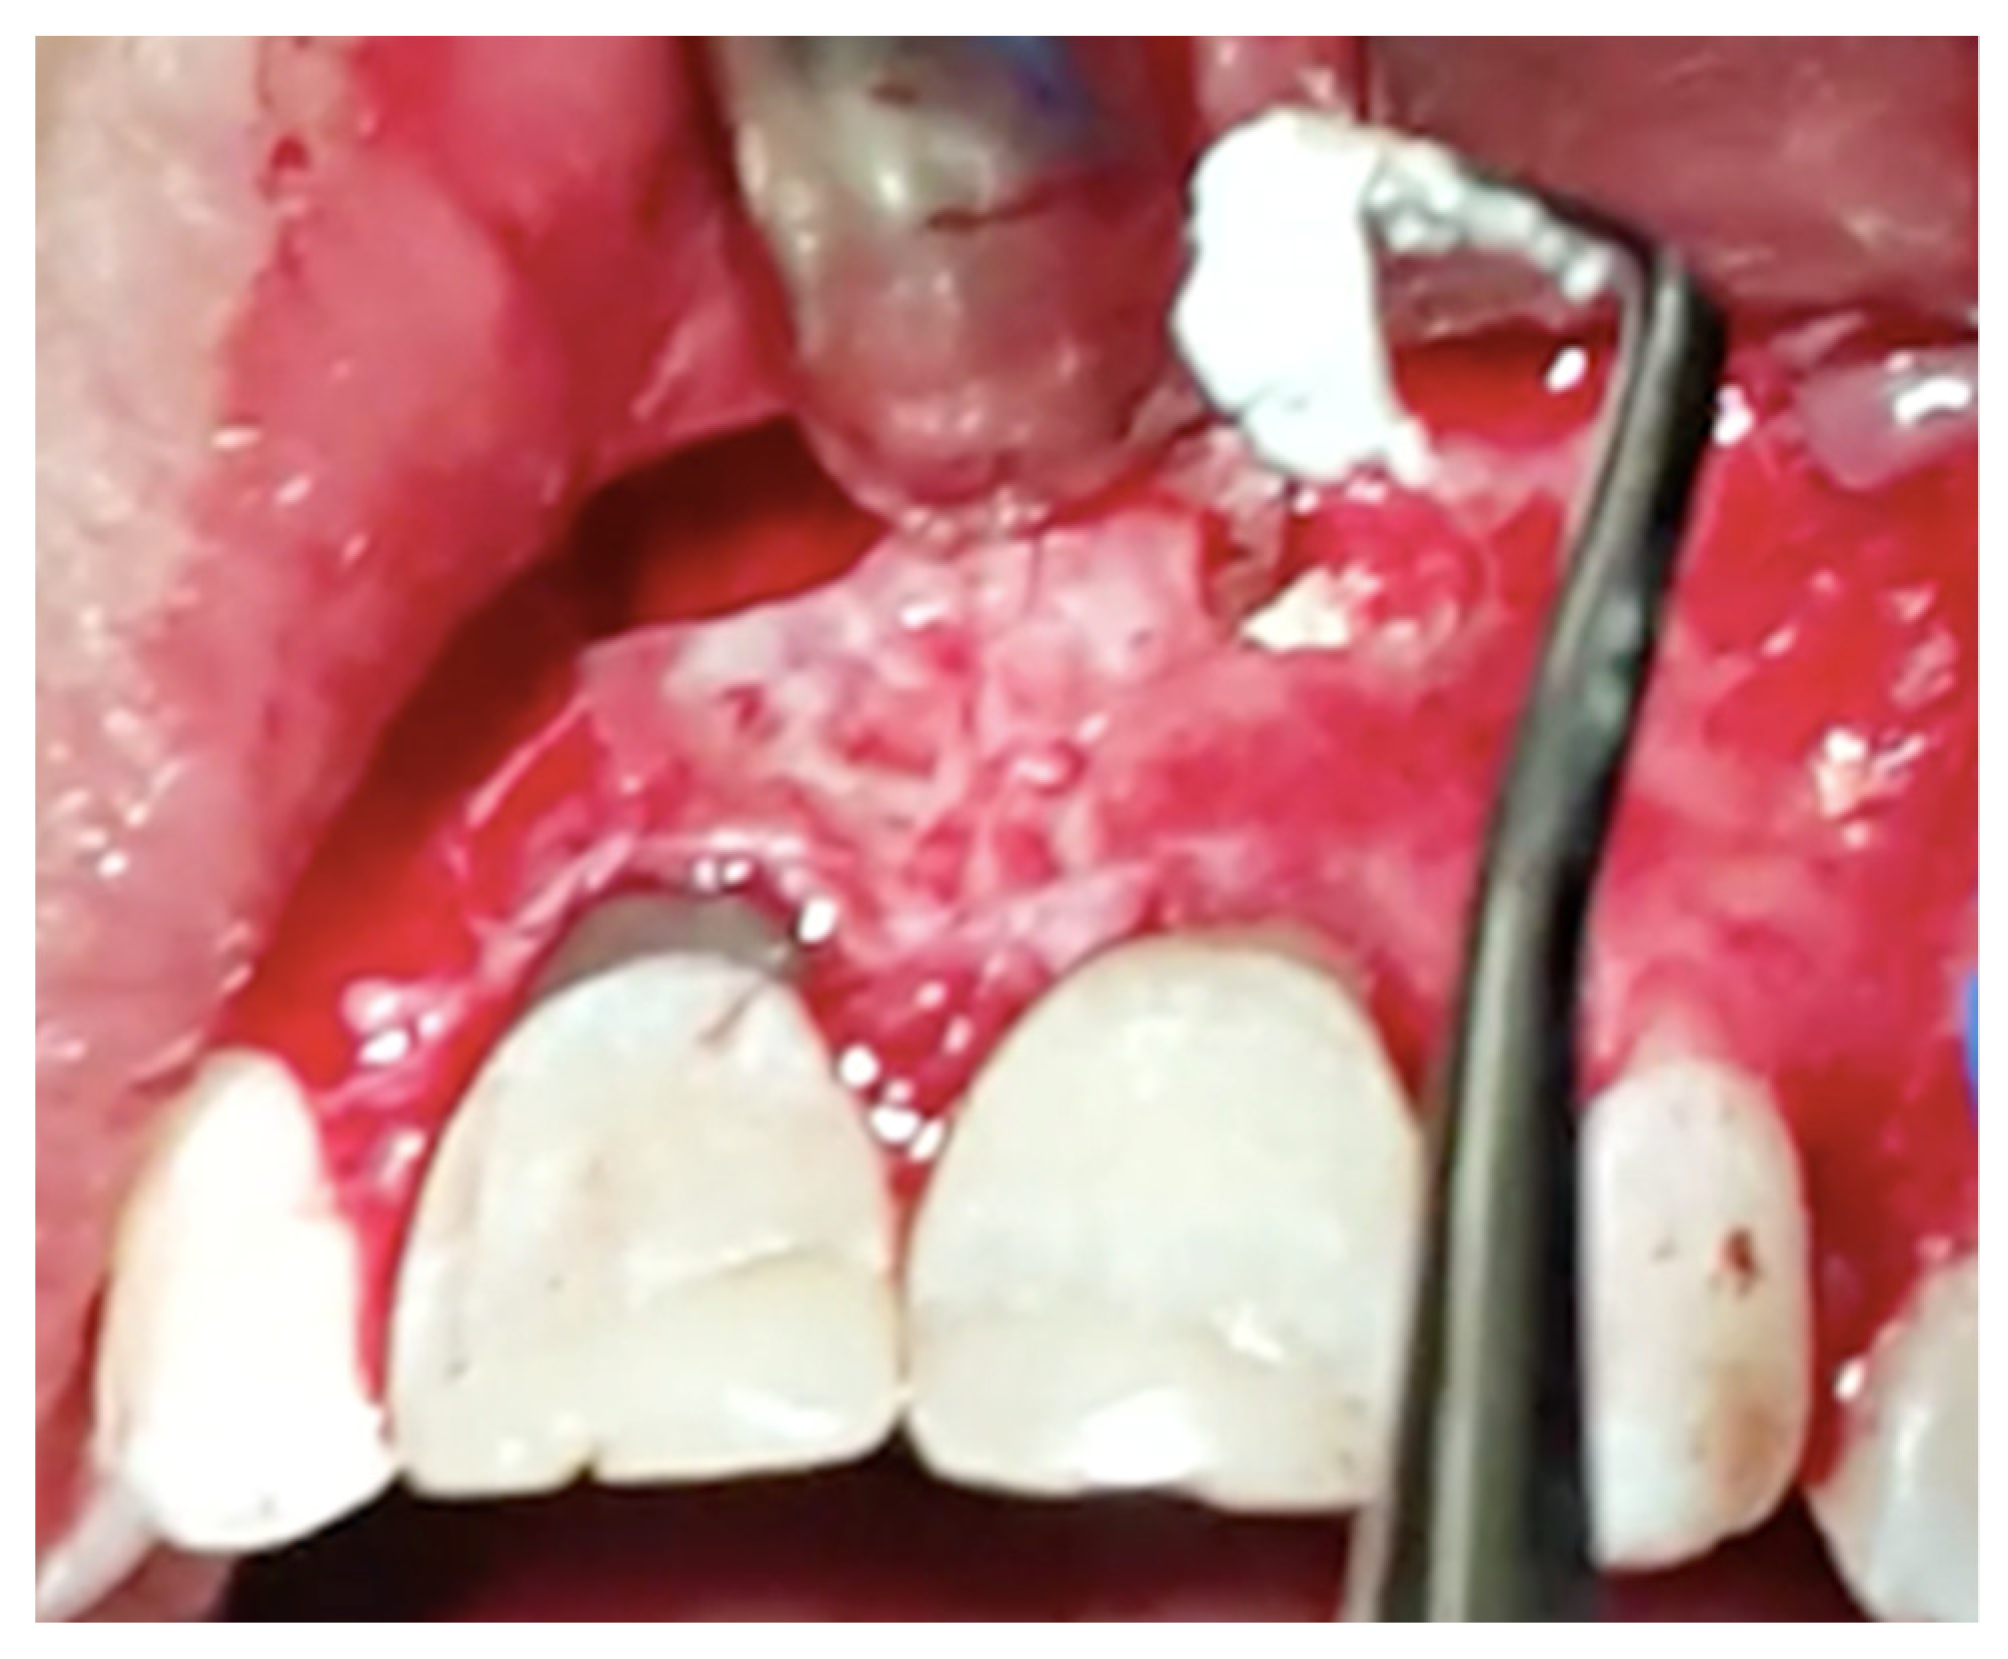

Figure 3.

Retrograde cavity preparation was performed by zirconia-coated ultrasonic tip used for periapical surgery.